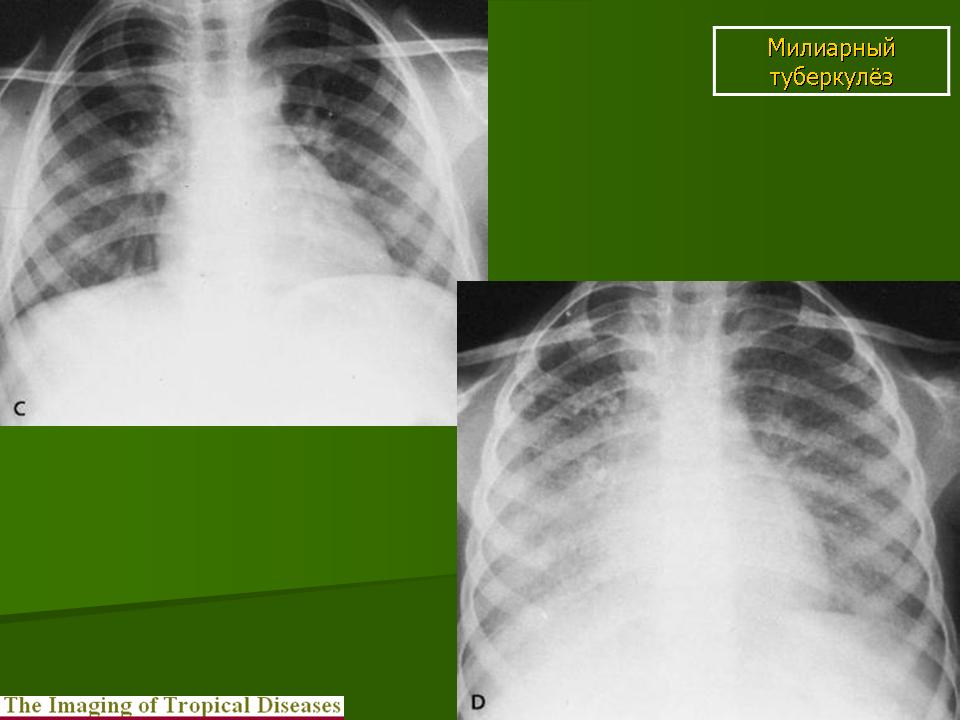

Микроскопический взгляд на мишитарный туберкулез легкого: фотодокументация

Раздел: Снимки-откровения